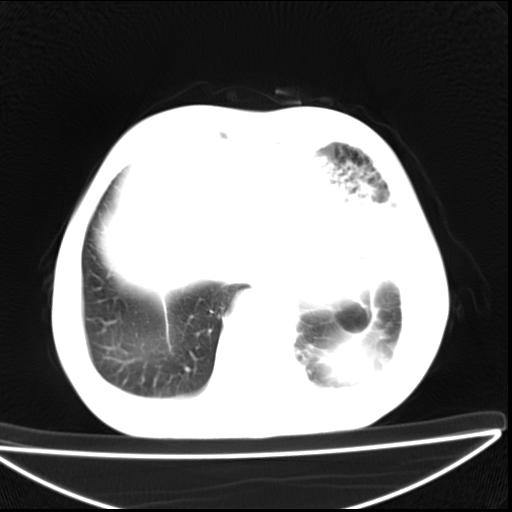

男  70岁,发烧咳嗽4天。盗汗,消瘦。无痰中带血丝,以前有肺tb病史,ct见,双肺tb,左侧胸廓塌陷,左胸膜肥厚粘连。纵隔移位,右侧胸腔积液,大家说说那个心影前左肺舌叶除了肺大炮还有炎症还是干酪性肺炎?有占位吗?我看纵隔淋巴结也大。

双肺继发性肺结核伴部分左肺毁损!

1)两肺继发性肺结核并左肺上叶肺不张,支气管扩张。2)双侧胸膜炎(胸膜增厚+少量胸腔积液)。

两肺继发性肺结核并感染,左肺上叶肺不张。建议ct增强。